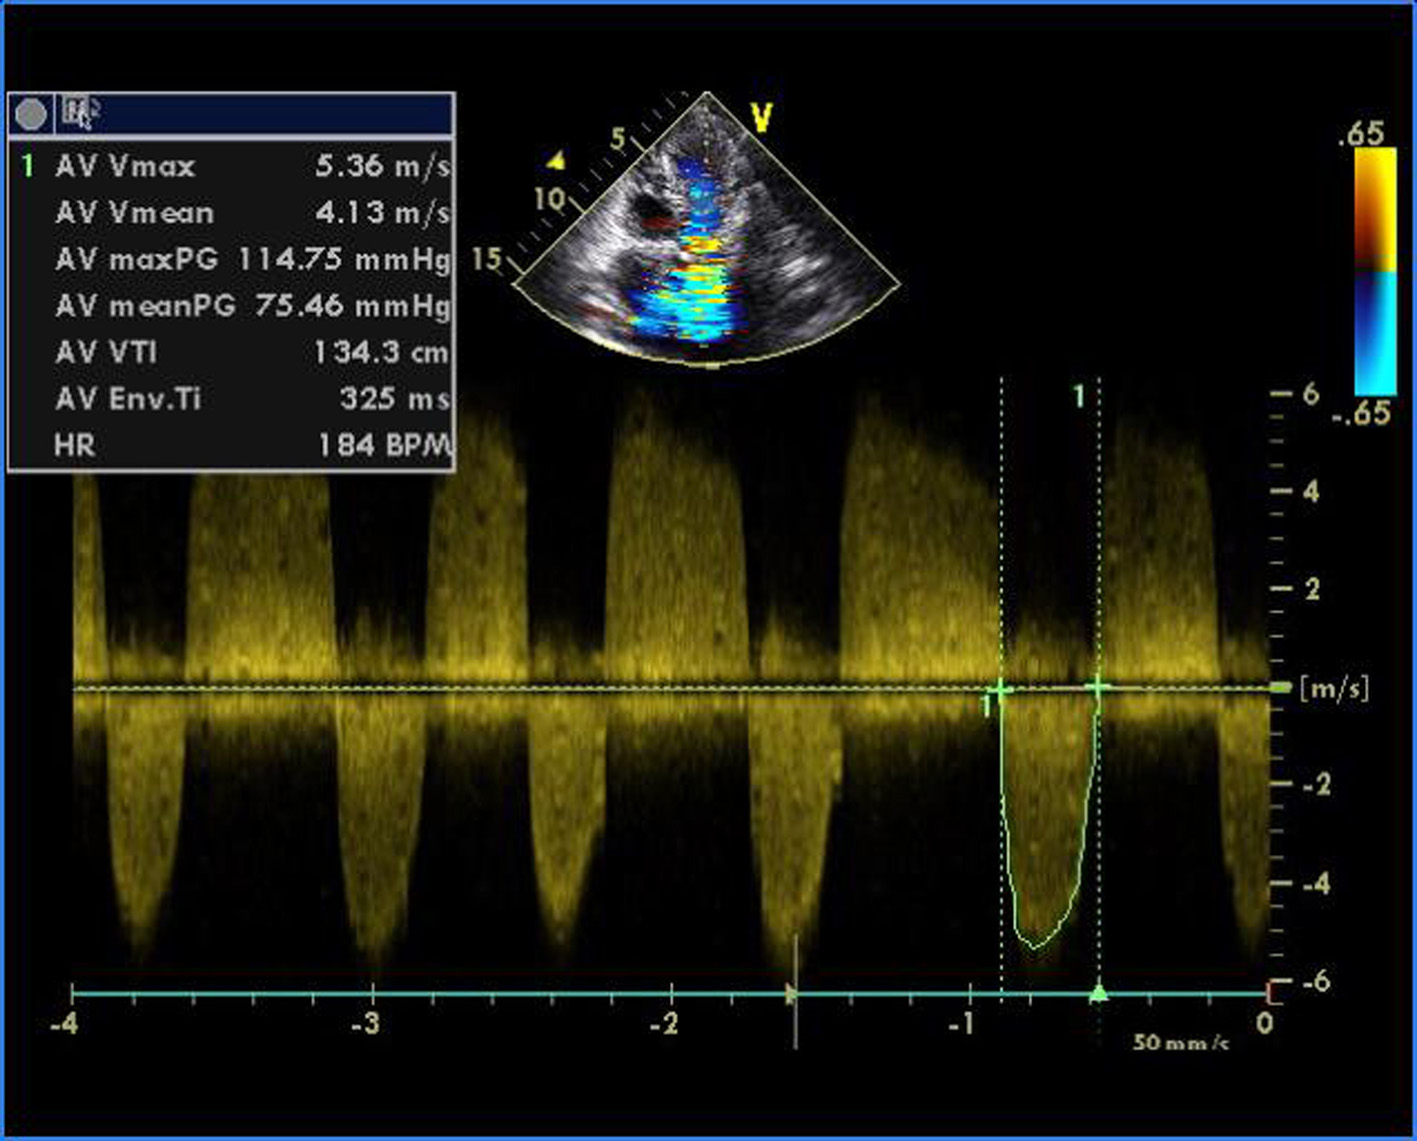

Figure 1. Transthoracic echocardiogram of apical four-chamber view showing thickened and doming mitral valve and tricuspid valve.